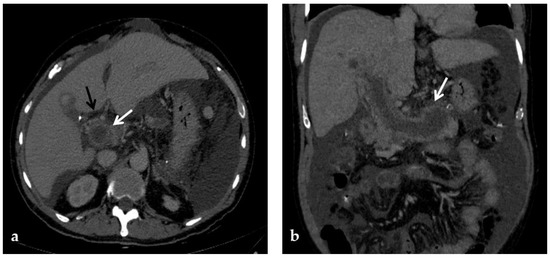

A CT scan in the pre-contrast phase can show hyperattenuating material in the portal vein. After contrast injection, lack of luminal enhancement increased portal vein caliber, increased arterial hepatic enhancement, and decreased portal hepatic enhancement are typical findings of PVT [28] (Figure 3 and Figure 4). Transient hepatic attenuation differences related to altered hepatic perfusion can also be demonstrated on CT with geographic areas of increased attenuation at the periphery of the liver on arterial phase imaging. These transient attenuation differences are related to decreased portal venous perfusion and compensatory increased arterial perfusion from the periphery of the liver [46,49].

Figure 4.

CT images of portal vein thrombosis in a 62-year-old male affected by myelofibrosis, who presented with intense abdominal pain. (a) Portal phase axial CT image shows a lack of luminal enhancement in the porta hepatis, increased portal vein caliber with enhancing walls, and a low-attenuating thrombus within the lumen, consistent with acute portal vein thrombosis (white arrow). Multiple collateral vessels forming a cavernoma are seen at the hepatic hilum (black arrow). (b) Portal phase coronal CT image better shows the extension of portal vein thrombosis, also involving the splenic vein (arrow).